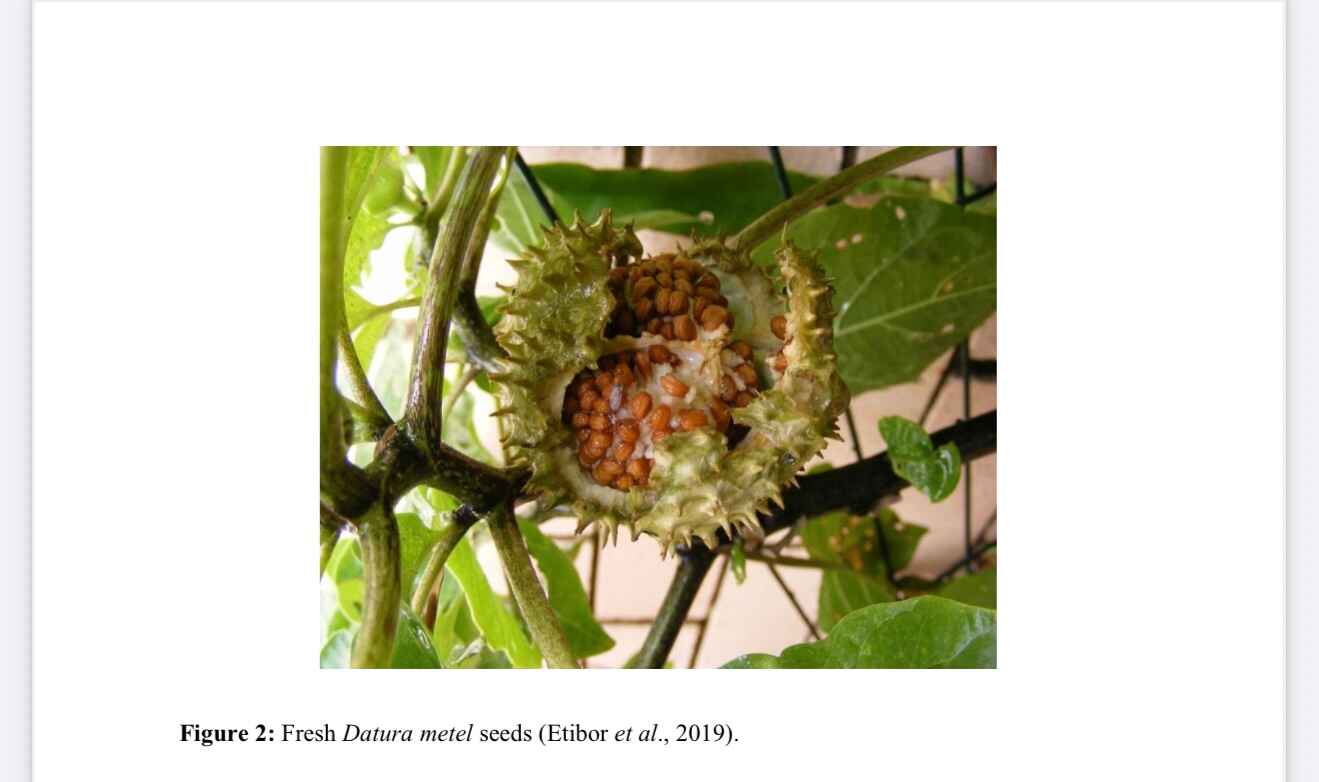

Effect of Hydro Ethanolic Seed Extract of Datura Metel on the Histology and Biochemistry of Liver Tissue of Sprague Dawley Rats